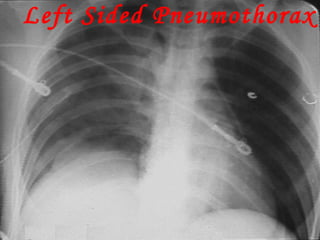

Left Sided Pneumothorax

PNEUMOTHORAX